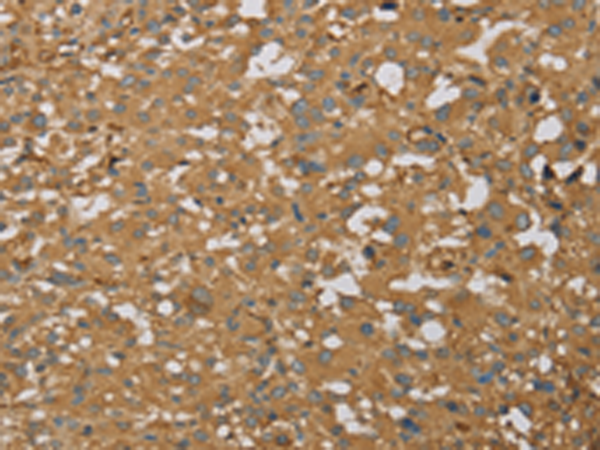

IHC positive control: |

Human thyroid cancer and Human brain |

IHC Recommend dilution: |

50-200 |